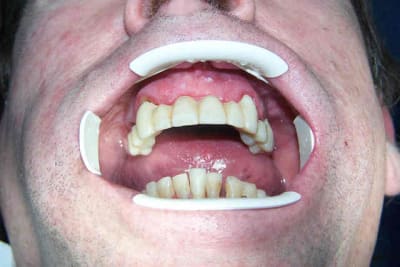

Il vient me voir en Janvier, avec son "bridge provisoire" qui bouge en haut. Il en a marre, il veut quelque chose de bien avec lequel il ne passe pas ses journées à craindre de perdre son truc lors de son show... Son partiel une dent du bas lui convient parfaitement.

(je joins la pano et deux photos, je précise qu'en rétroalvéolaire, les racines antérieures et prémolaires en haut sont "bonnes" même si la dépose de magnifiques RCR compos infiltrés donne l'illusion du contraire)

Vous avez quoi avec le chiffre 4 ? j'ai 5 piliers en haut (15 13 23 24 25).